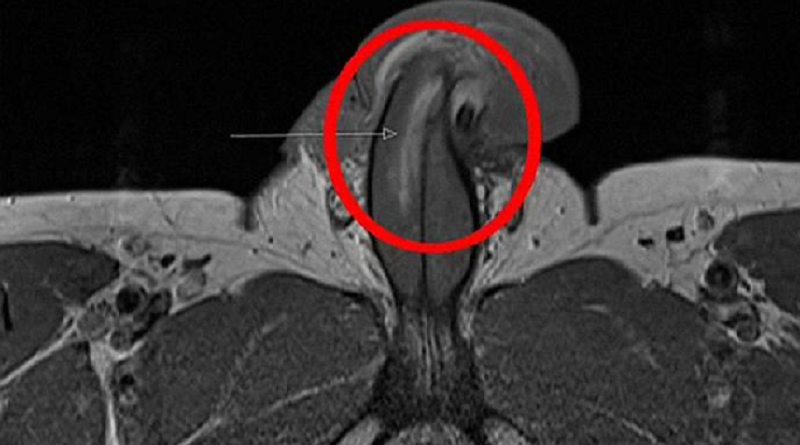

Mas, neste caso, ele dividiu a túnica albugínea – a camada protetora em torno do tecido erétil que bombeia o sangue para essa área.

O médico disse que nenhum som de “estalo” foi ouvido quando a quebra ocorreu, o que acontece quando as fraturas são horizontais.

Mas o pênis do paciente gradualmente inchou após o ferimento.